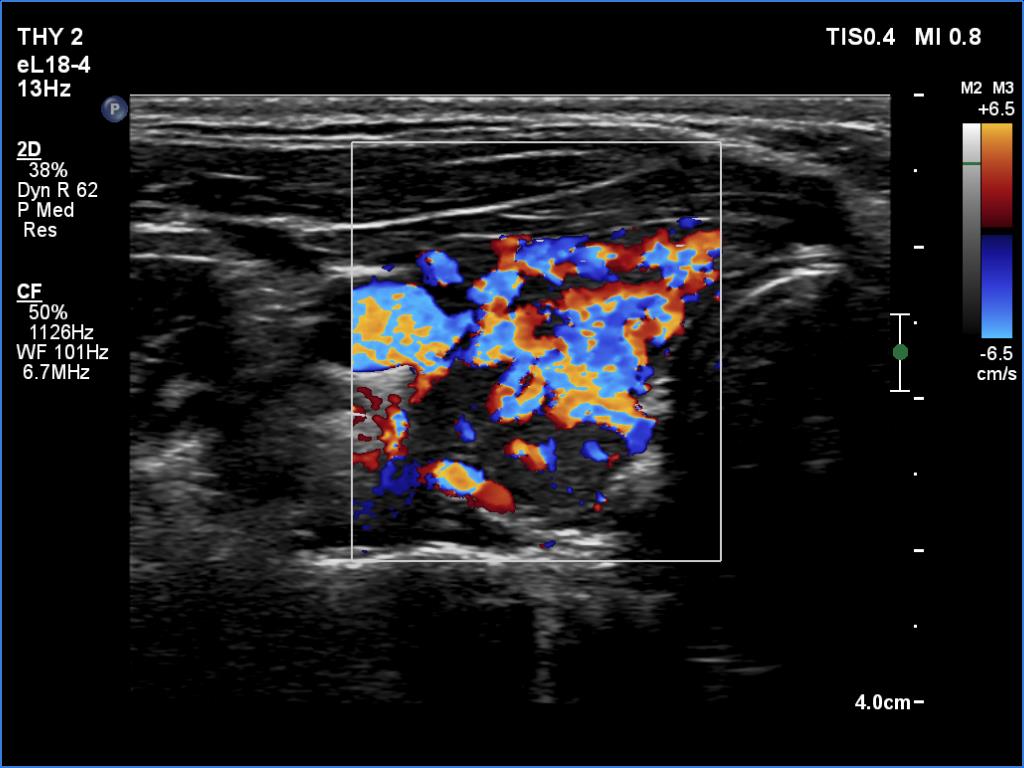

Ultrasonography. The thyroid was moderately hypoechoic and inhomogeneous. There was a deeply hypoechoic lesion in the isthmus which presented microcalcifications. Compared with the extranodular tissue, the nodule was much less vascularized on Doppler and microflow imaging but was harder on elastography.